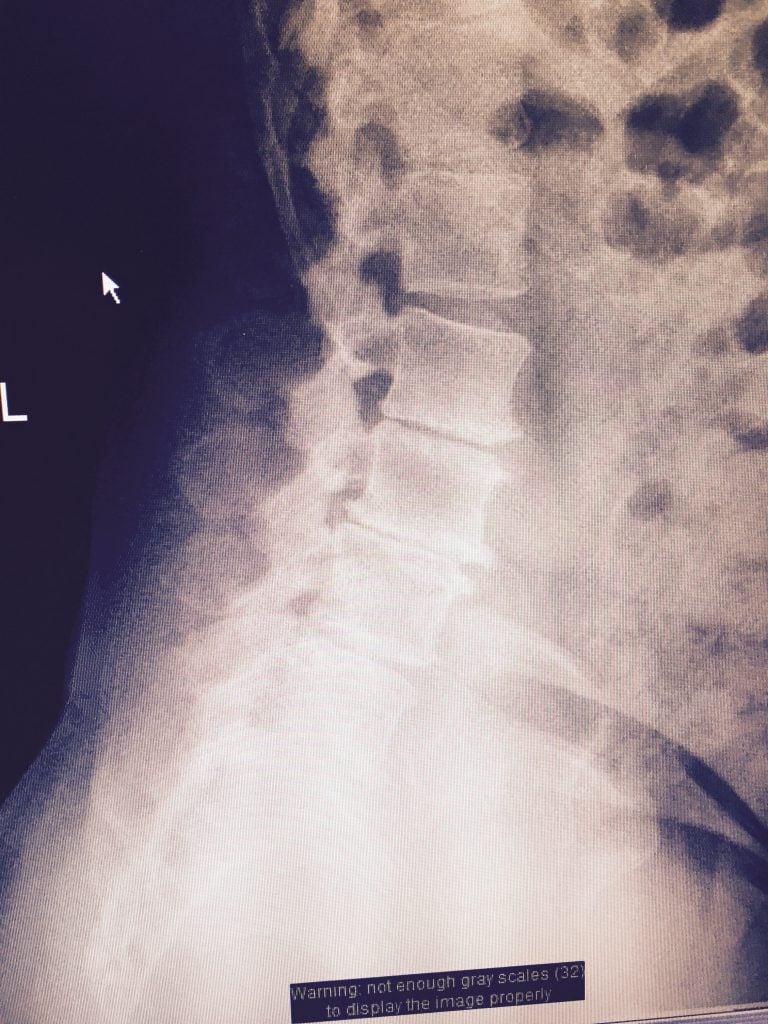

I am a medical doctor so I am in a good position to know who is a truly good doctor. I had lower back pain, muscle stiffness and neurological symptoms for a number of years. I tried every type of therapy but the problem was too extensive. The MRI showed every type of pathology. All the surgeons said the surgery couldn't be done minimally invasively. I found Dr. Qureshi by nothing short of divine guidance. He is one of ten surgeons across the country that is able to do such extensive pathology minimally invasively without cutting muscle. The surgery was 100 percent successful. The results were miraculous. I have no pain or disability. With a rod and ten screws in my back I can exercise as if I never had a problem. I am so indebted to to Dr. Qureshi - I could never fully express my gratitude. He is also a kind and humble man. I am evidence of Dr. Qureshi's greatness.